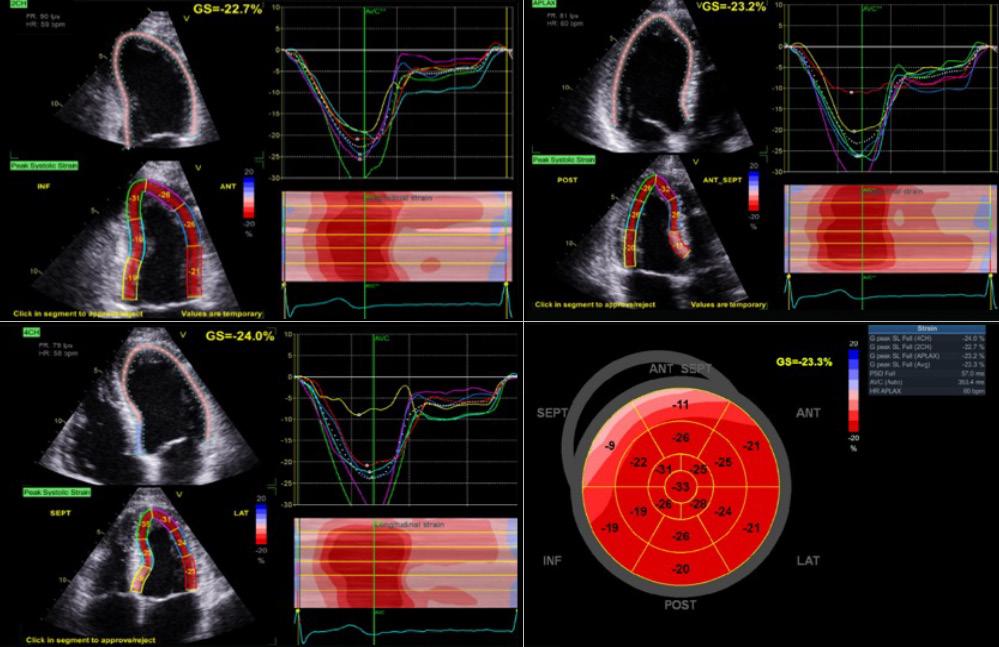

L’imagerie cardiaque est un défi pour plusieurs raisons. Une routine de base est établie pour ce type d’examen. Elle consiste en des vues parasternales, long et court axe, ainsi qu’en des vues apicales et souscostales (figure 1). L’anatomie et la fonction des valves et des ventricules sont étudiées. La fraction d’éjection, les gradients aortiques, mitraux, tricuspides et pulmonaires sont tous des aspects qui sont évalués et mesurés en cours d’examen. Les pathologies complexes observées seront imagées de façon encore plus détaillée dans le but de les définir davantage, souvent en utilisant des fonctions d’intelligence artificielle sur les appareils, par exemple, par imagerie du strain myocardique (figure 2).

Au cours de la réalisation de l’échocardiographie post-coronarographie et post-implantation d’un tuteur actif, le strain longitudinal global est altéré (-23.3 %), ce qui indique un strain normal. Un strain longitudinal global <12 % a été suggéré pour indiquer un dysfonctionnement systolique sévère et une valeur <15-16 %, un risque chez les patients dont la fraction d’éjection est préservée.